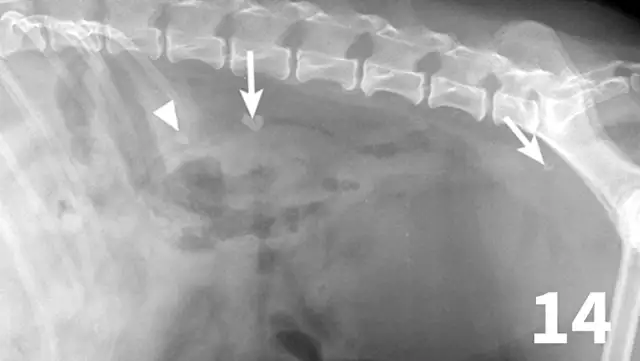

Normal ureters cannot be visualized with survey radiography or ultrasonography, but normal and abnormal ureters are readily visualized with excretory urography. The location of a ureteral obstruction or rupture as well as the presence of an ectopic ureter (especially when combined with pneumocystography) can be documented with excretory urography (Figure 11). A dilated ureter (hydroureter) can be observed with ultrasonography (Figure 12). Pyelocentesis (for cytology and culture) and antegrade pyelography (nephropyelography) (Figure 13) to document obstruction or leakage can be conducted via ultrasound guidance with heavy sedation or anesthesia. Ultrasonography can also be used to visualize retroperitoneal fluid accumulation, which may occur with a ureteral rupture, hemorrhage, or infectious or neoplastic disease. Whereas ureteroliths without hydroureter may be missed on ultrasonography, radiopaque ureteroliths can be observed on survey radiography (Figure 14). Survey radiographic visualization of radiopaque ureteroliths may be facilitated by enemas to empty the colon of fecal material and/or use of a radiolucent paddle to apply regional compression over the ureter to separate adjacent organs (eg, loops of bowel) (Figure 15). Aged cats with chronic kidney disease (CKD) frequently have calcium oxalate nephroliths; in some cases, these nephroliths will migrate into the ureters. Survey radiographs should be employed to rule out ureterolithiasis, especially in cats with acute decompensation of their CKD (Figure 16).